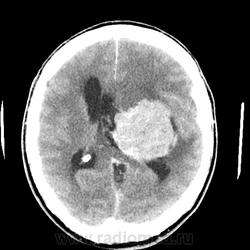

Мужчина 66 лет. Поступил с подозрением на ОНМК. Жалобы на атаксию и когнитивные нарушения (родственники рассказали о его плохой памяти, рассеянности, забывчивости, в последнее время, а также о нарушении речи и невнятности в произношении "мямлил"). Объемное образование в теменной, височной доли и базальных ядрах слева. Вазогенный отек. Выраженный масс-эффект. Латеральная дислокация вправо на 1,5см. Не могу дифференцировать интравентрикулярно ли, субэпендимарно ли расположено или за счет такого масс-эффекта? Ипсилатеральный желудочек компремирован, контрлатеральный компенсаторно расширен, височные рога боковых желудочков расширены, III желудочек значительно сужен и не дифференцируется, IVинтактен. Сильвиев водопровод сужен, достоверно не дифференцируется, супраселлярная цистерна сужена. Субарахноидальные борозды и конвекситальные пространства сужены. Выраженно диффузно очень интенсивно накапливает КВ. DDs: более вероятно: менингиома,  менее вероятно: субэпендимарная АСЦ, анапластическая АСЦ, глиобластома. Сложилось впечатление с большей вероятностью о внутрижелудочковой менингиоме с экстравентрикулярным ростом.

Почему внутрижелудочковая? Видно же, что она желудочек просто компремирует.

А так видно, что опухоль растет изнутри расширяя желудочек.

Для сравнения внутримозговая гематома, которая реально компремирует.

Она растет из сосудистого сплетения заднего рога левого бокового желудочка, поэтому его расширяет, а вот передний рог как раз компремирует

Согласна, не убедительно. Мне не кажется, что внутрижелудочковая. По-моему желудочек подбавлен.